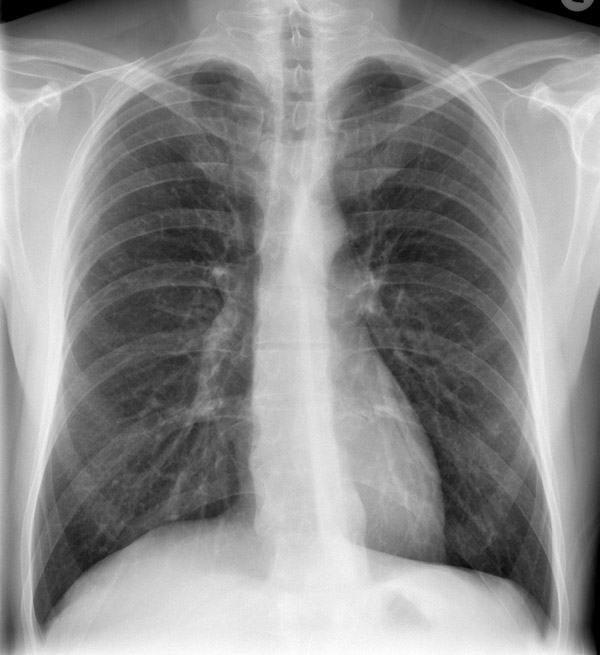

-

рентгеновский снимок: локализация в верхнем сегменте левой нижней доли

На рентгене определяются изменения бронхов и легочного интерстиция, а также очаговая, сегментарная или долевая инфильтрация, воспалительные уплотнения, усиление легочного рисунка. Чаще эти изменения обнаруживают с одной стороны в нижних легочных полях.

Воспаление легких, вызванное C. Pneumoniae (по некоторым данным, это около 10 % всех случаев), относится к атипичным пневмониям. У них нет специфических симптомов, и течение заболевания похоже на микоплазменную инфекцию. Клиническая картина болезни характеризуется постепенным развитием и начинается с воспаления верхних дыхательных путей, сухого кашля и повышения температуры. У таких пациентов на рентгенограмме легких выявляются небольшие сегментарные инфильтраты, а в анализе крови часто отсутствует увеличение количества лейкоцитов. У пожилых людей инфекция может протекать до такой степени тяжело, что иногда требуется немедленная госпитализация.